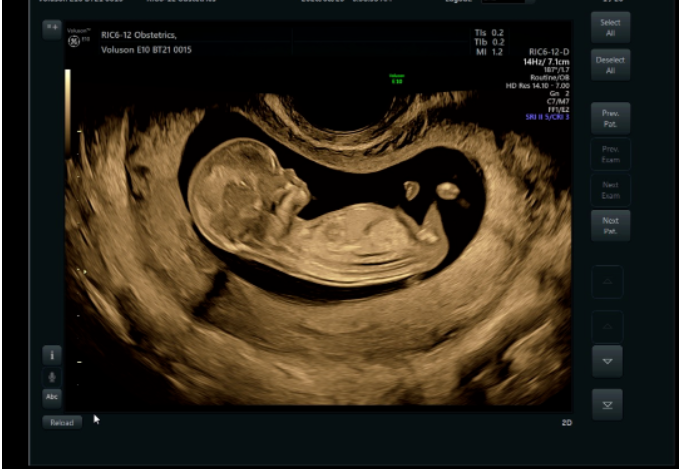

相较普通四维彩超,E10的高清画质堪比IMAX电影大片!

过去的四维彩超常常看到胎宝宝就像个“小泥人”,只能看看大致轮廓;E10四维彩超,可以实现您与宝宝的超高清“隔空对视”,直接观察他们的一举一动、乖巧秀容,包括:皱眉、微笑、打哈欠、吸吮和吞咽、小腿交叉盘坐等,提前享受为人父母的喜悦。